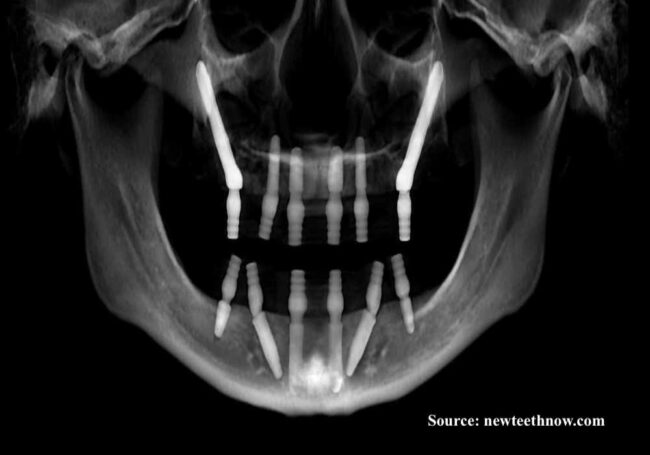

Dental implants being the most shielded alternative for the people that are replacing with lost or damaged teeth. As like a natural tooth it unites with the underlying bone and offers support, which also gives natural appearances.